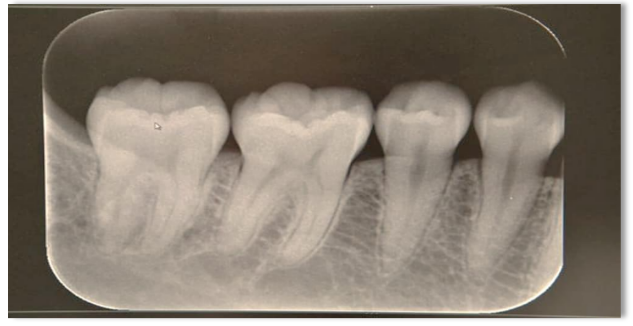

A utilização de exames de imagem como as Radiografias periapicais (Figura 6), interproximais e panorâmicas, se mostram como métodos largamente empregados e que contribuem para fornecer uma boa visualização da estrutura do dente e osso adjacente, além de favorecer uma análise forense mais apurada dos detalhes da arcada dentária, como facilitam a comparação de registros odontológicos em prontuários, aumentando as possibilidades dos registros post mortem (Nagare et al., 2018).

Figura 6 – Radiografias periapicais

Fonte: Ademar Júnior, 2022

Para identificação humana por meio das radiografias odontológicas, são necessárias comparações de registros das radiografias tiradas em vida e arquivadas nos consultórios odontológicos e as obtidas após a morte, para comparação das características anatômicas, como tamanho e forma das coroas, anatomia pulpar, e posição e forma da crista do osso alveolar, além das características resultantes dos tratamentos dentários, como restaurações, tratamentos endodônticos e próteses (Ramos et al., 2021)